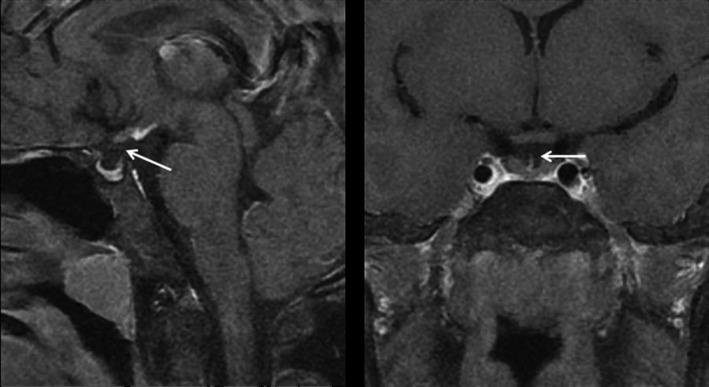

Pituitary stalk interruption syndrome (PSIS) is a rare type of hypopituitarism manifesting various degrees of pituitary hormone deficiency. Although mutations have been identified in some familial cases, the underpinning mechanisms of sporadic patients with PSIS who are in a vast majority remain elusive, necessitating a comprehensive study using systemic approaches. We postulate that other genetic mechanisms may be responsible for the sporadic PSIS. To test this hypothesis, we conducted a study in 24 patients with PSIS of Han Chinese with no family history using whole-exome sequencing (WES) and bioinformatic analysis. We identified a group of heterozygous mutations in 92% (22 of 24) of the patients, and these genes are mostly associated with Notch, Shh, Wnt signalling pathways. Importantly, 83% (20 of 24) of the patients had more than one mutation in those pathways suggesting synergy of compound mutations underpin the pathogenesis of sporadic PSIS.

垂体柄中断综合征(PSIS)是一种罕见的垂体功能减退症,表现为不同程度的垂体激素缺乏。虽然在一些家族性病例中已经发现了突变,但绝大多数散发性 PSIS 患者的潜在机制仍难以捉摸,需要使用系统方法进行全面研究。我们假设其他遗传机制可能与散发性 PSIS 有关。为了验证这一假说,我们使用全外显子组测序(WES)和生物信息学分析对 24 名无家族史的汉族 PSIS 患者进行了研究。我们在 92%(22/24)的患者中发现了一组杂合突变,这些基因主要与 Notch、Shh、Wnt 信号通路有关。重要的是,83%(20/24)的患者在这些通路中存在不止一种突变,这表明复合突变的协同作用是散发性 PSIS 发病机制的基础。